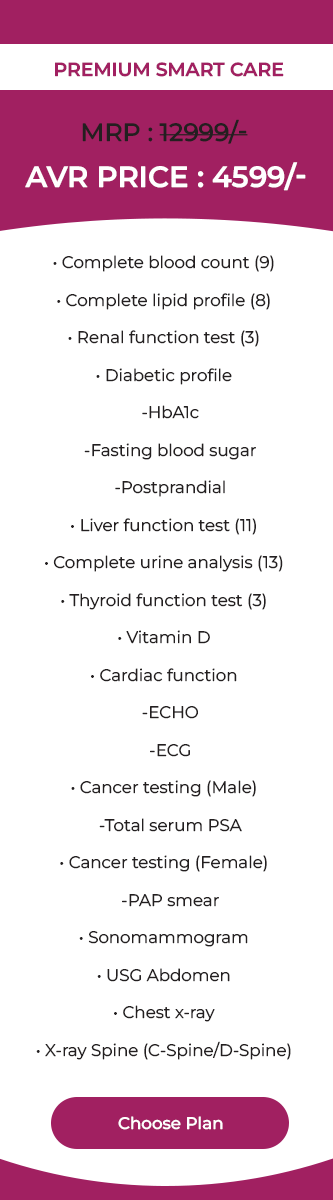

Welcome to AVR Scan

Our doctors are on call 24/7. Same Day Appointments Available.

High-End Technology

State-of-the-art technology We are using at AVR Scan